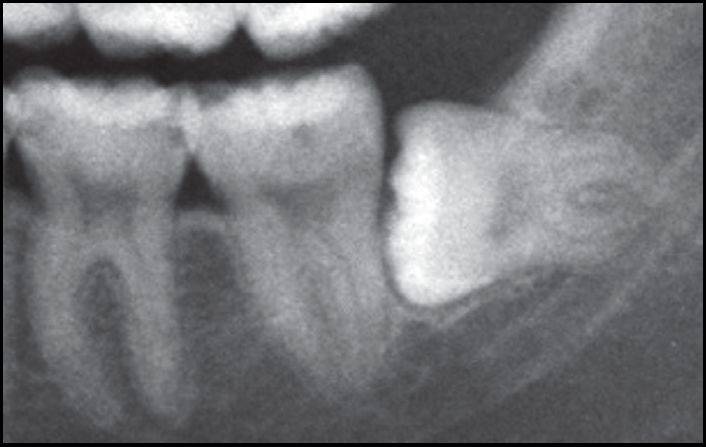

单根牙、根分叉不大者、合并根、融合根、特短根、锥形根阻力较小。若根尖区向远中弯曲、无弯曲或根尖未形成,则阻力也较小。

根部阻力较小的智齿形态

根周骨阻力以骨质增生和牙根有骨粘连者阻力较大,根周骨质疏松、有炎症性骨吸收者阻力较小。